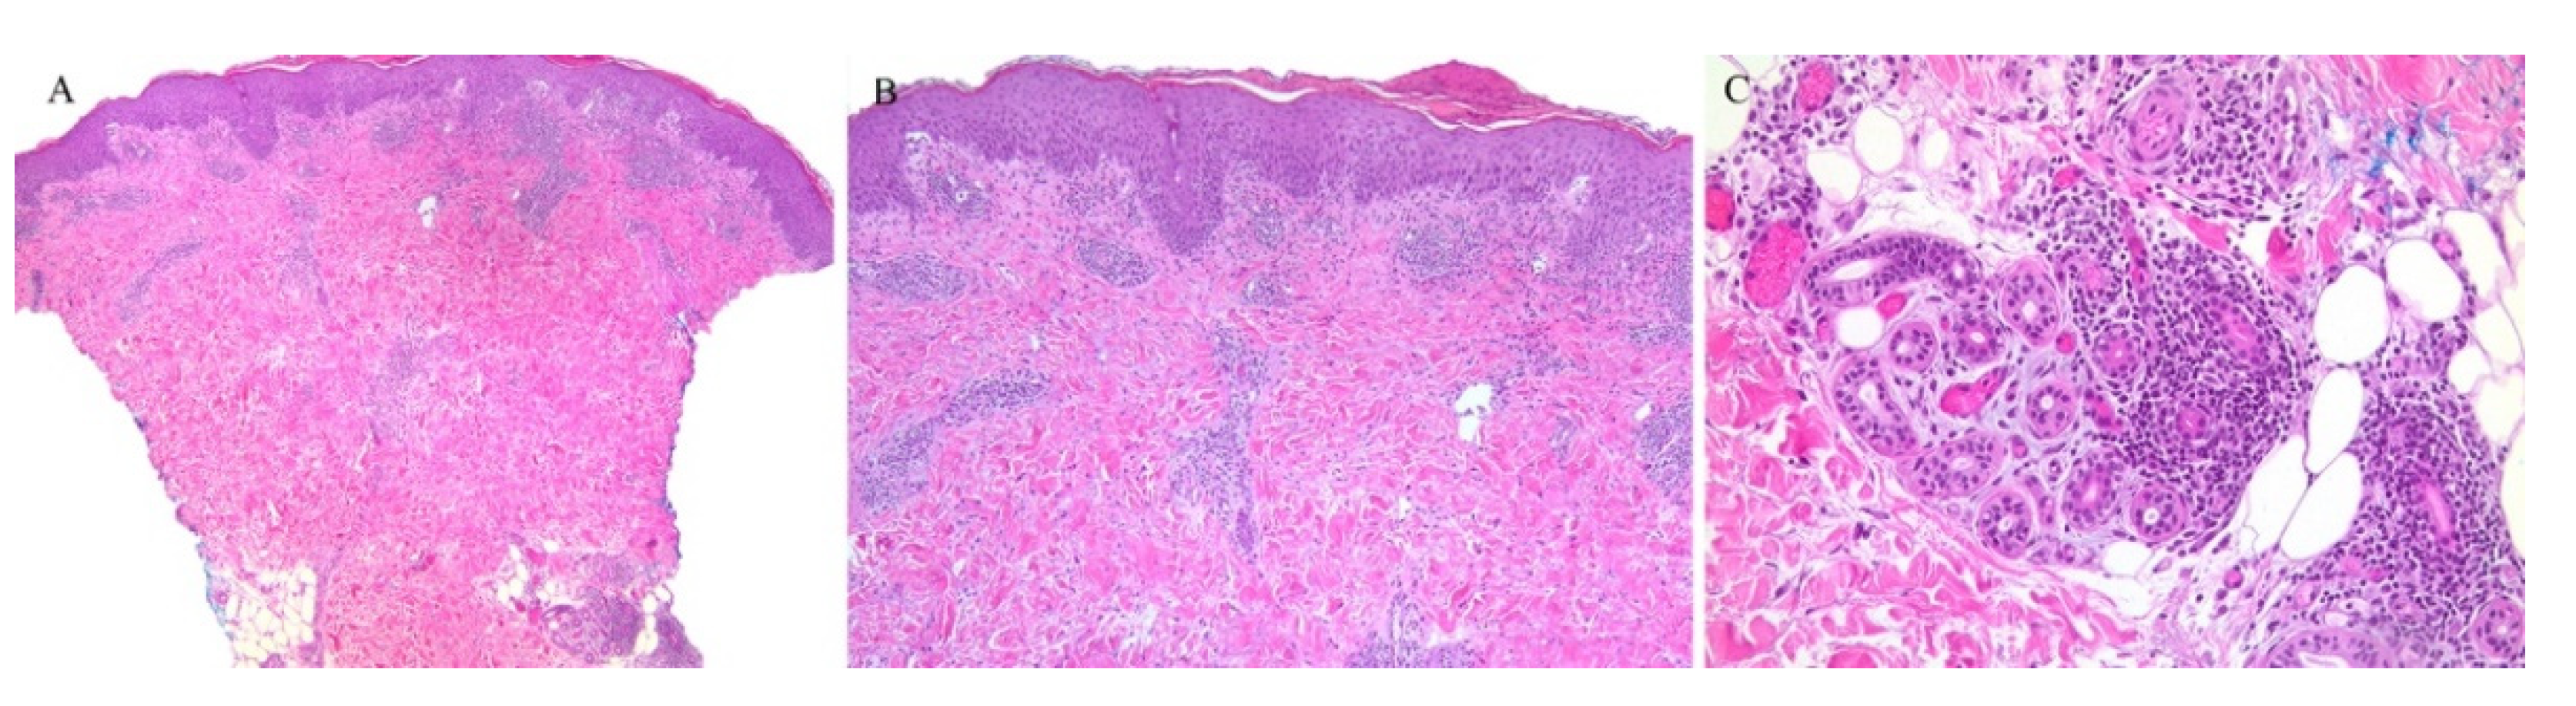

Clinically, the involvement of the hair follicle in GVHD can result in a variety of manifestations including non-scarring and scarring alopecias, a follicular rash, and comedonal lesions, among others [11]. Histologically, follicular variants have been described in both acute and chronic forms of GVHD (Figure 2) [12]. Unfortunately, the reported cases of acute follicular GVHD carried a high mortality rate while chronic follicular GVHD seems to confer a more favorable prognosis [13,14]. This involvement of the follicular epithelium has been attributed to inflammation around the bulge region of the hair follicle, likely due to the presence of stem cells in this area [15].

Figure 2.

(A–C) Graft versus host disease with perieccrine inflammation.

Eccrine gland involvement is also seen in GVHD. In addition to the classical histologic features, a lymphoplasmacytic infiltrate around the eccrine coils is a specific feature of GVHD (Figure 2) [16]. Eccrine squamous syringometaplasia has also been described in biopsy specimens of a patient with cutaneous and hepatic GVHD [17].